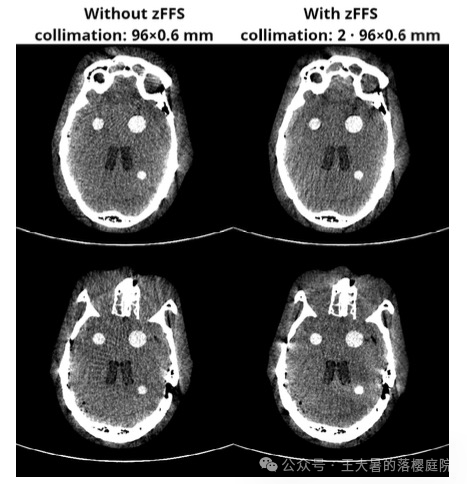

使用和不使用z轴飞焦点功能(z-flying focal spot ,zFFS)得到的图像如下图所示: